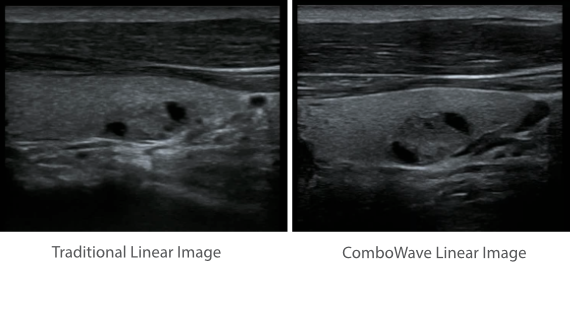

Klinische Bilder